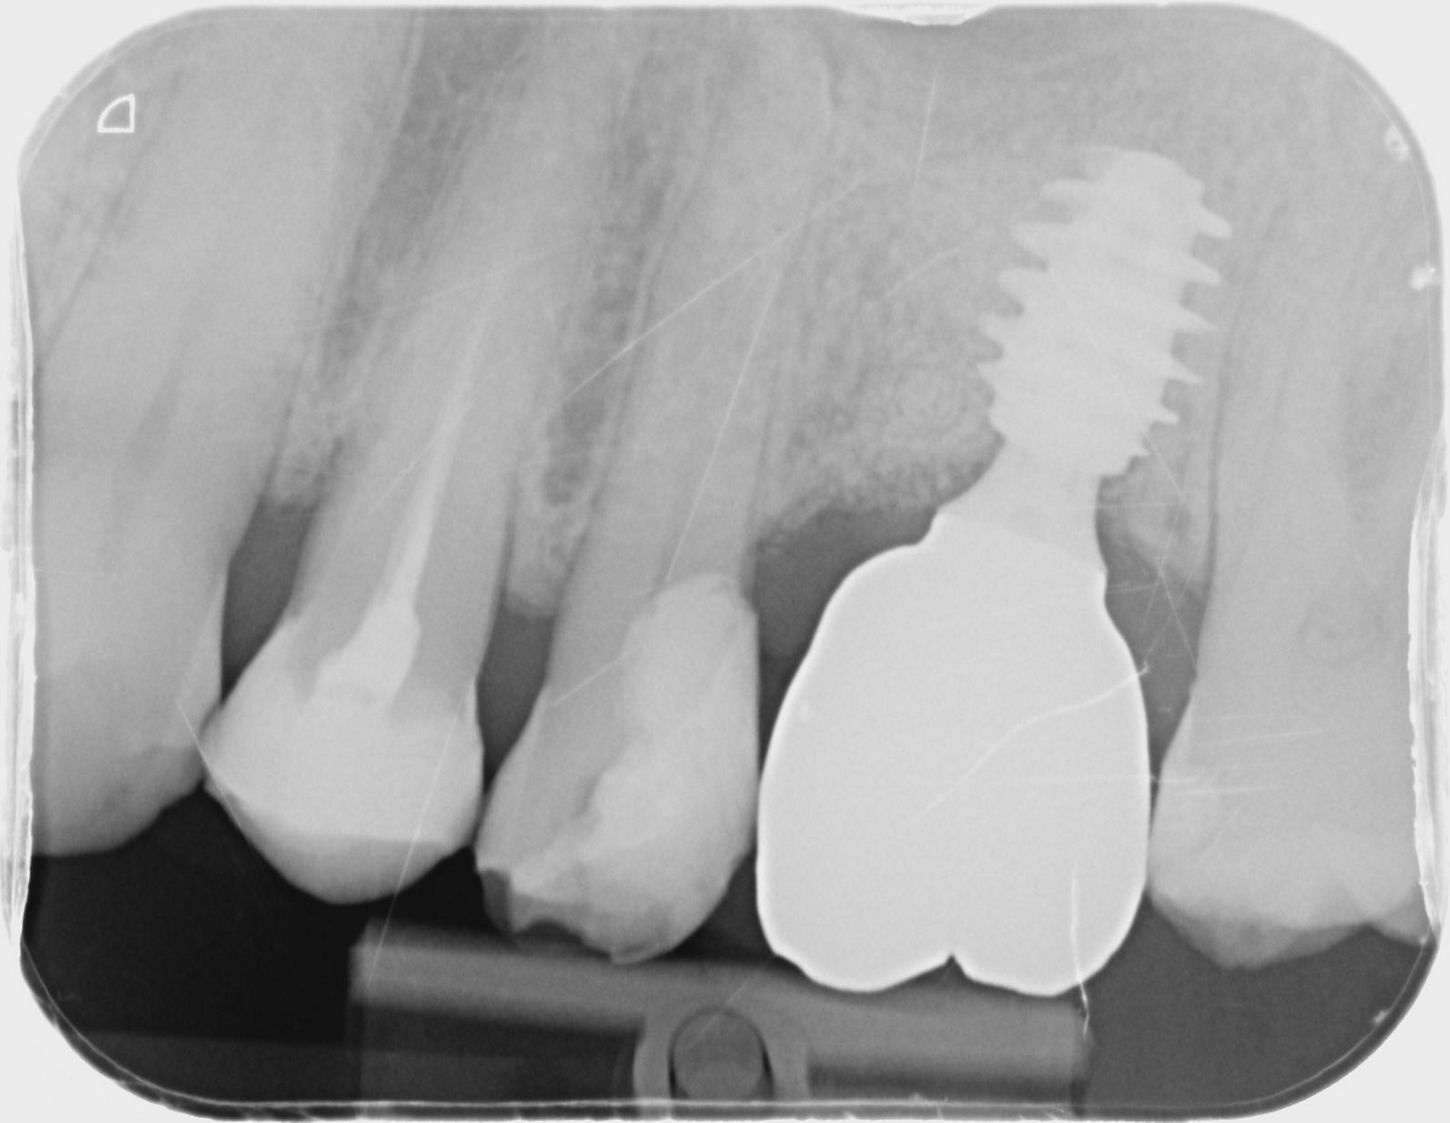

11a. 11b. Radiographs of the SSA in place and scan body for digital impressions.

11a

11b